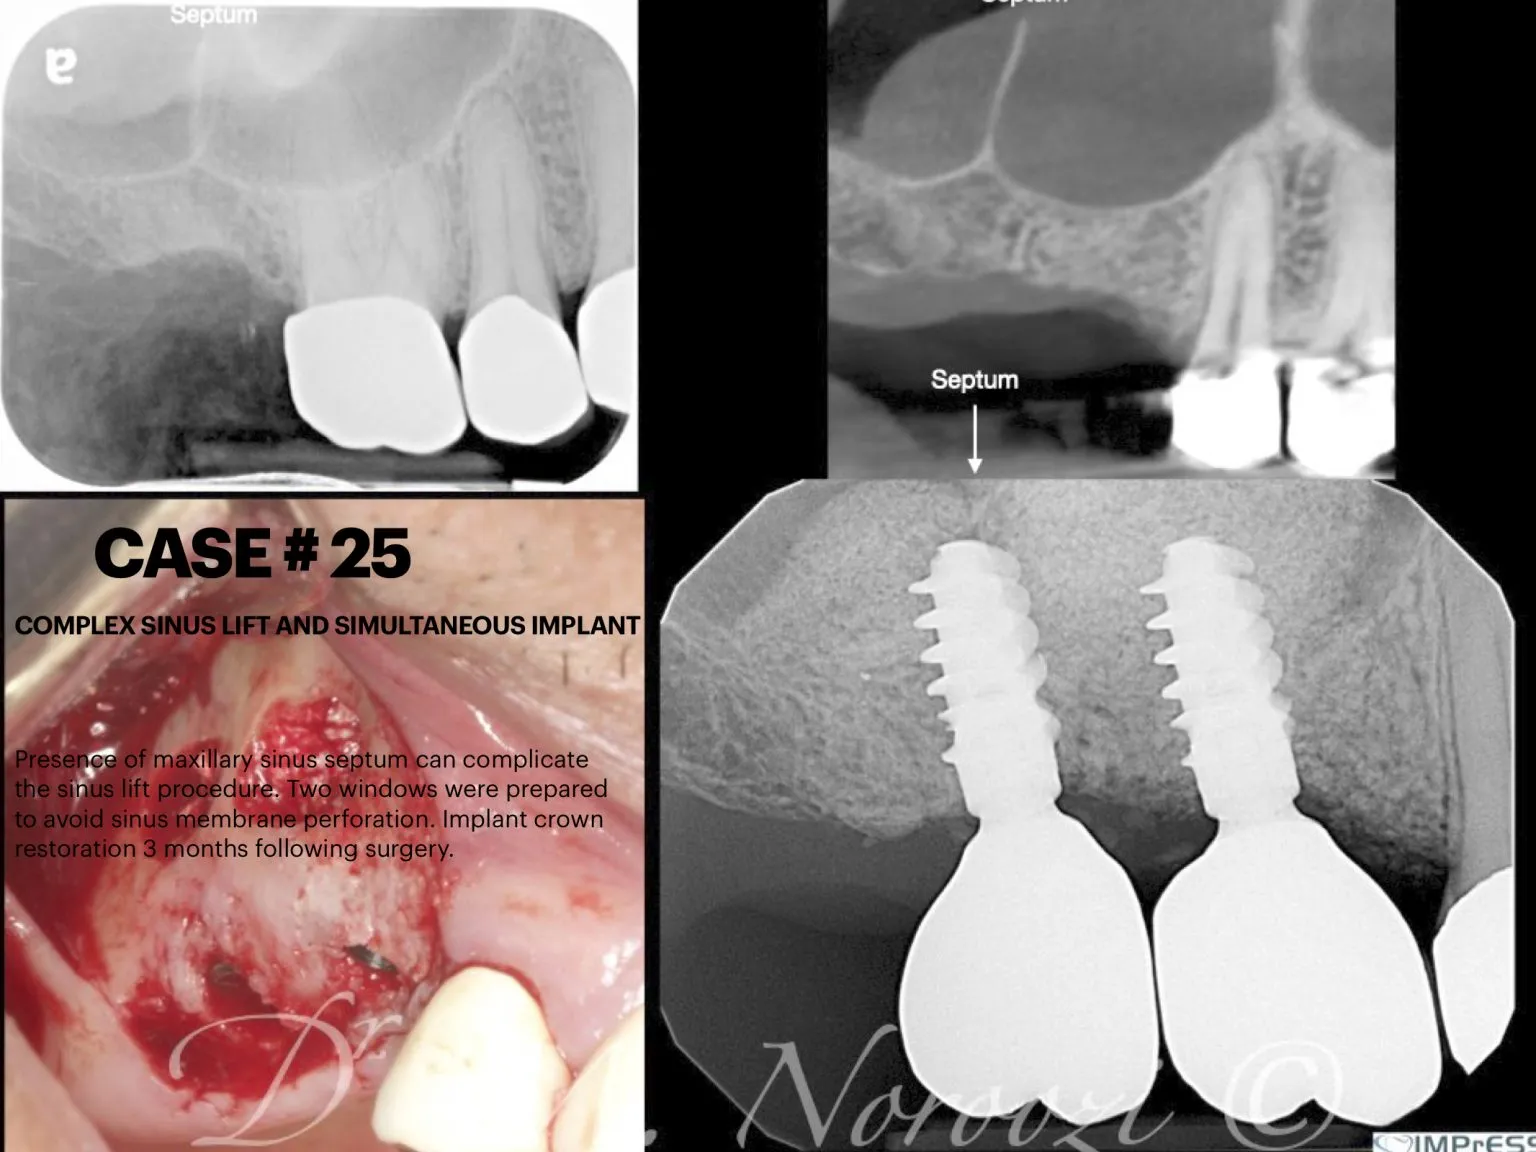

Sinus & Implant Surgery

Dental Implant Centre in Vancouver Burnaby Sinus Lift Dental implant Surgery Dr. Noroozi Implant Specialist IMPrESS Perio Implant Center.001

Sinus Lift, Bone Graft, Implants Dr. Noroozi IMPrESS Perio Implant Center